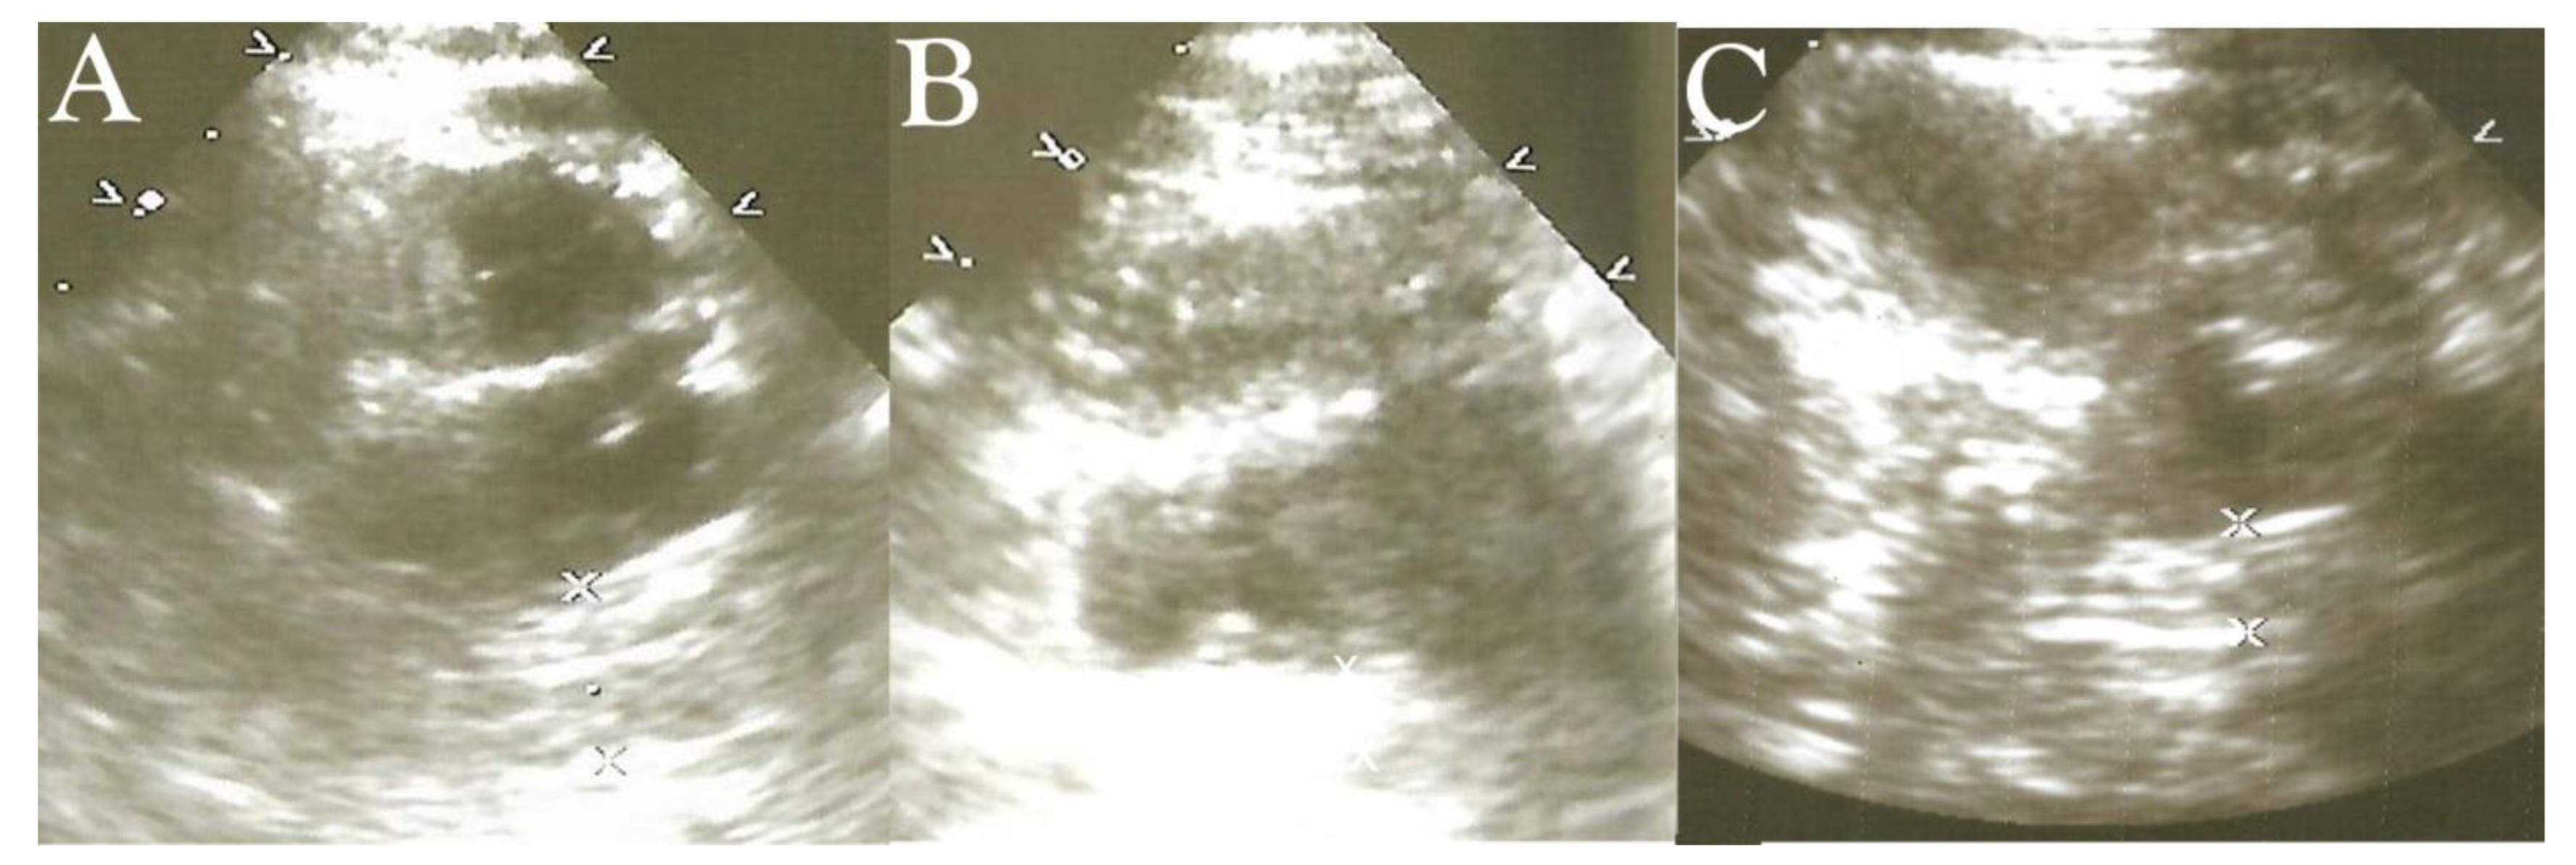

- Njemanze, P.C. , Njemanze J., Skelton A., Akudo A., Akagha O., Chukwu A.A ; et al. High-frequency ultrasound imaging of the duodenum and colon in patients with symptomatic giardiasis in comparison to amebiasis and healthy subjects. J Gastroenterol Hepatol 2008;23:e34-42. [CrossRef]

- Njemanze, P.C. , Njemanze J.T., Ofoegbu C.C., Darlington C.C., Nneke E., Onweni J.A.; et al. High-frequency ultrasound imaging of the intestine in normal subjects and patients with intestinal parasites. In: Ali Abdo Gamie S, Mahmoud Foda E, editors. Essentials of Abdominal Ultrasound. London: IntechOpen; 2019; pp. 91–105. [Google Scholar] [CrossRef]

- Njemanze, P.C. , Njemanze J.T., Ofoegbu C.C., Nneke E., Onweni I.A., Ejiogu U.V.; et al. Technical notes on high-frequency ultrasound duodenography and colonography imaging of giardial lesions. Niger J Gen Pract 2021;19:54-60.